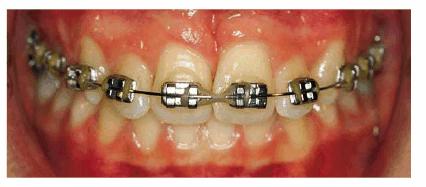

From an orthodontic perspective, a serious skeletal Class II with deep bite is becoming more and more evident. Therefore, orthodontic treatment has been initiated in both arches to align the dentition over the basal bone in harmony with the surrounding hard and soft tissues, as well as to achieve good esthetics (Figures 27-7F and G

Figure 27-7F and G: The same patient during the orthodontic treatment and after. Good esthetics has been achieved.

RESULT: The team work of several specialists created a good

morphic-functional recovery (Figures 27-11E and F) and an esthetic result that satisfied

the patient (Figures 27-11G and H).

Figure 27-11E and F: The morphic-functional recovery at the end of the orthodontic treatment.

Figure 27-11G and H: The final result showing the patient's smile at the end of the treatment.